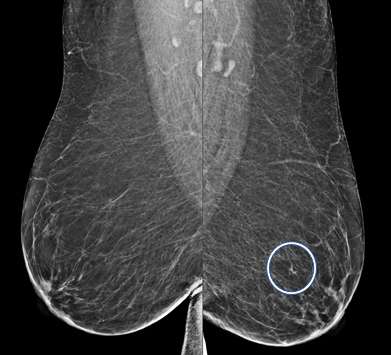

Asymmetry:

An asymmetry is a finding onlyseen on one projection3. Asymmetries that have been evaluated without suspicious features but persist are likely benign and can be managed with 6-month short-term imaging follow up.

MLO views of the breast demonstrate an asymmetry in the left subareolar breast, middle depth. This finding is called an asymmetry if there is no corresponding finding on the CC view.